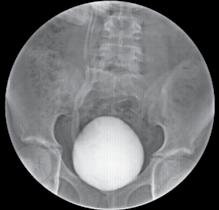

Materiale și metode: Un total de 49 de pacienți care s-au prezentat la camera de garda a Spitalului Clinic de Urgență „Sfântul Ioan” București cu patologie renală acută sugerând prezența unor calculi la nivel renal și/sau ureteral care au fost confirmați prin imagistică (radiografie, ultrasonografie sau tomografie computerizată) au fost incluși în acest studiu retrospectiv, în perioada septembrie 2021 – decembrie 2021. Toți pacienții selectați au avut indicație de intervenție de urgență și au fost tratați prin inserarea unui stent dublu J. Am analizat rata de stone-free după a doua intervenție, care a fost una dintre următoarele: ureteroscopie semirigidă, ureteroscopie flexibilă, ureteroscopie combinată semirigidă și flexibilă și PCNL. Pacienții s-au întors pentru a doua intervenție și au fost reevaluați imagistic.

Calculii pot fi diagnosticați folosind: Radiografia tractului renal (doar 60-70% dintre calculi sunt radio-opaci și, prin urmare, este posibil să se rateze diagnosticul unora dintre ei). Ecografia tractului renal poate fi utilă în depistarea calculilor renali și hidronefrozei, dar poate eșua pentru litiaza renala cu calculi mici și pentru litiaza ureterală, prin urmare nu este cea mai bună alegere în modalitatea imagistică aleasă în cazurile de colică acută. Pielografia intravenoasă poate fi o alegere pentru investigații în unitățile medicale unde este încă utilizată. Tehnicile de imagistică CT reprezintă investigația standard de aur pentru a evalua prima prezentare a colicii renale [3] .